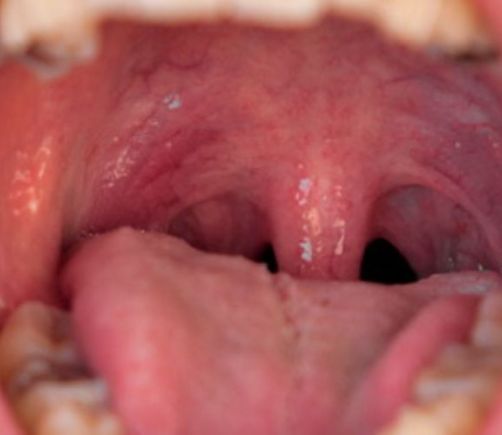

La infección por el VPH puede causar cáncer de boca y de garganta